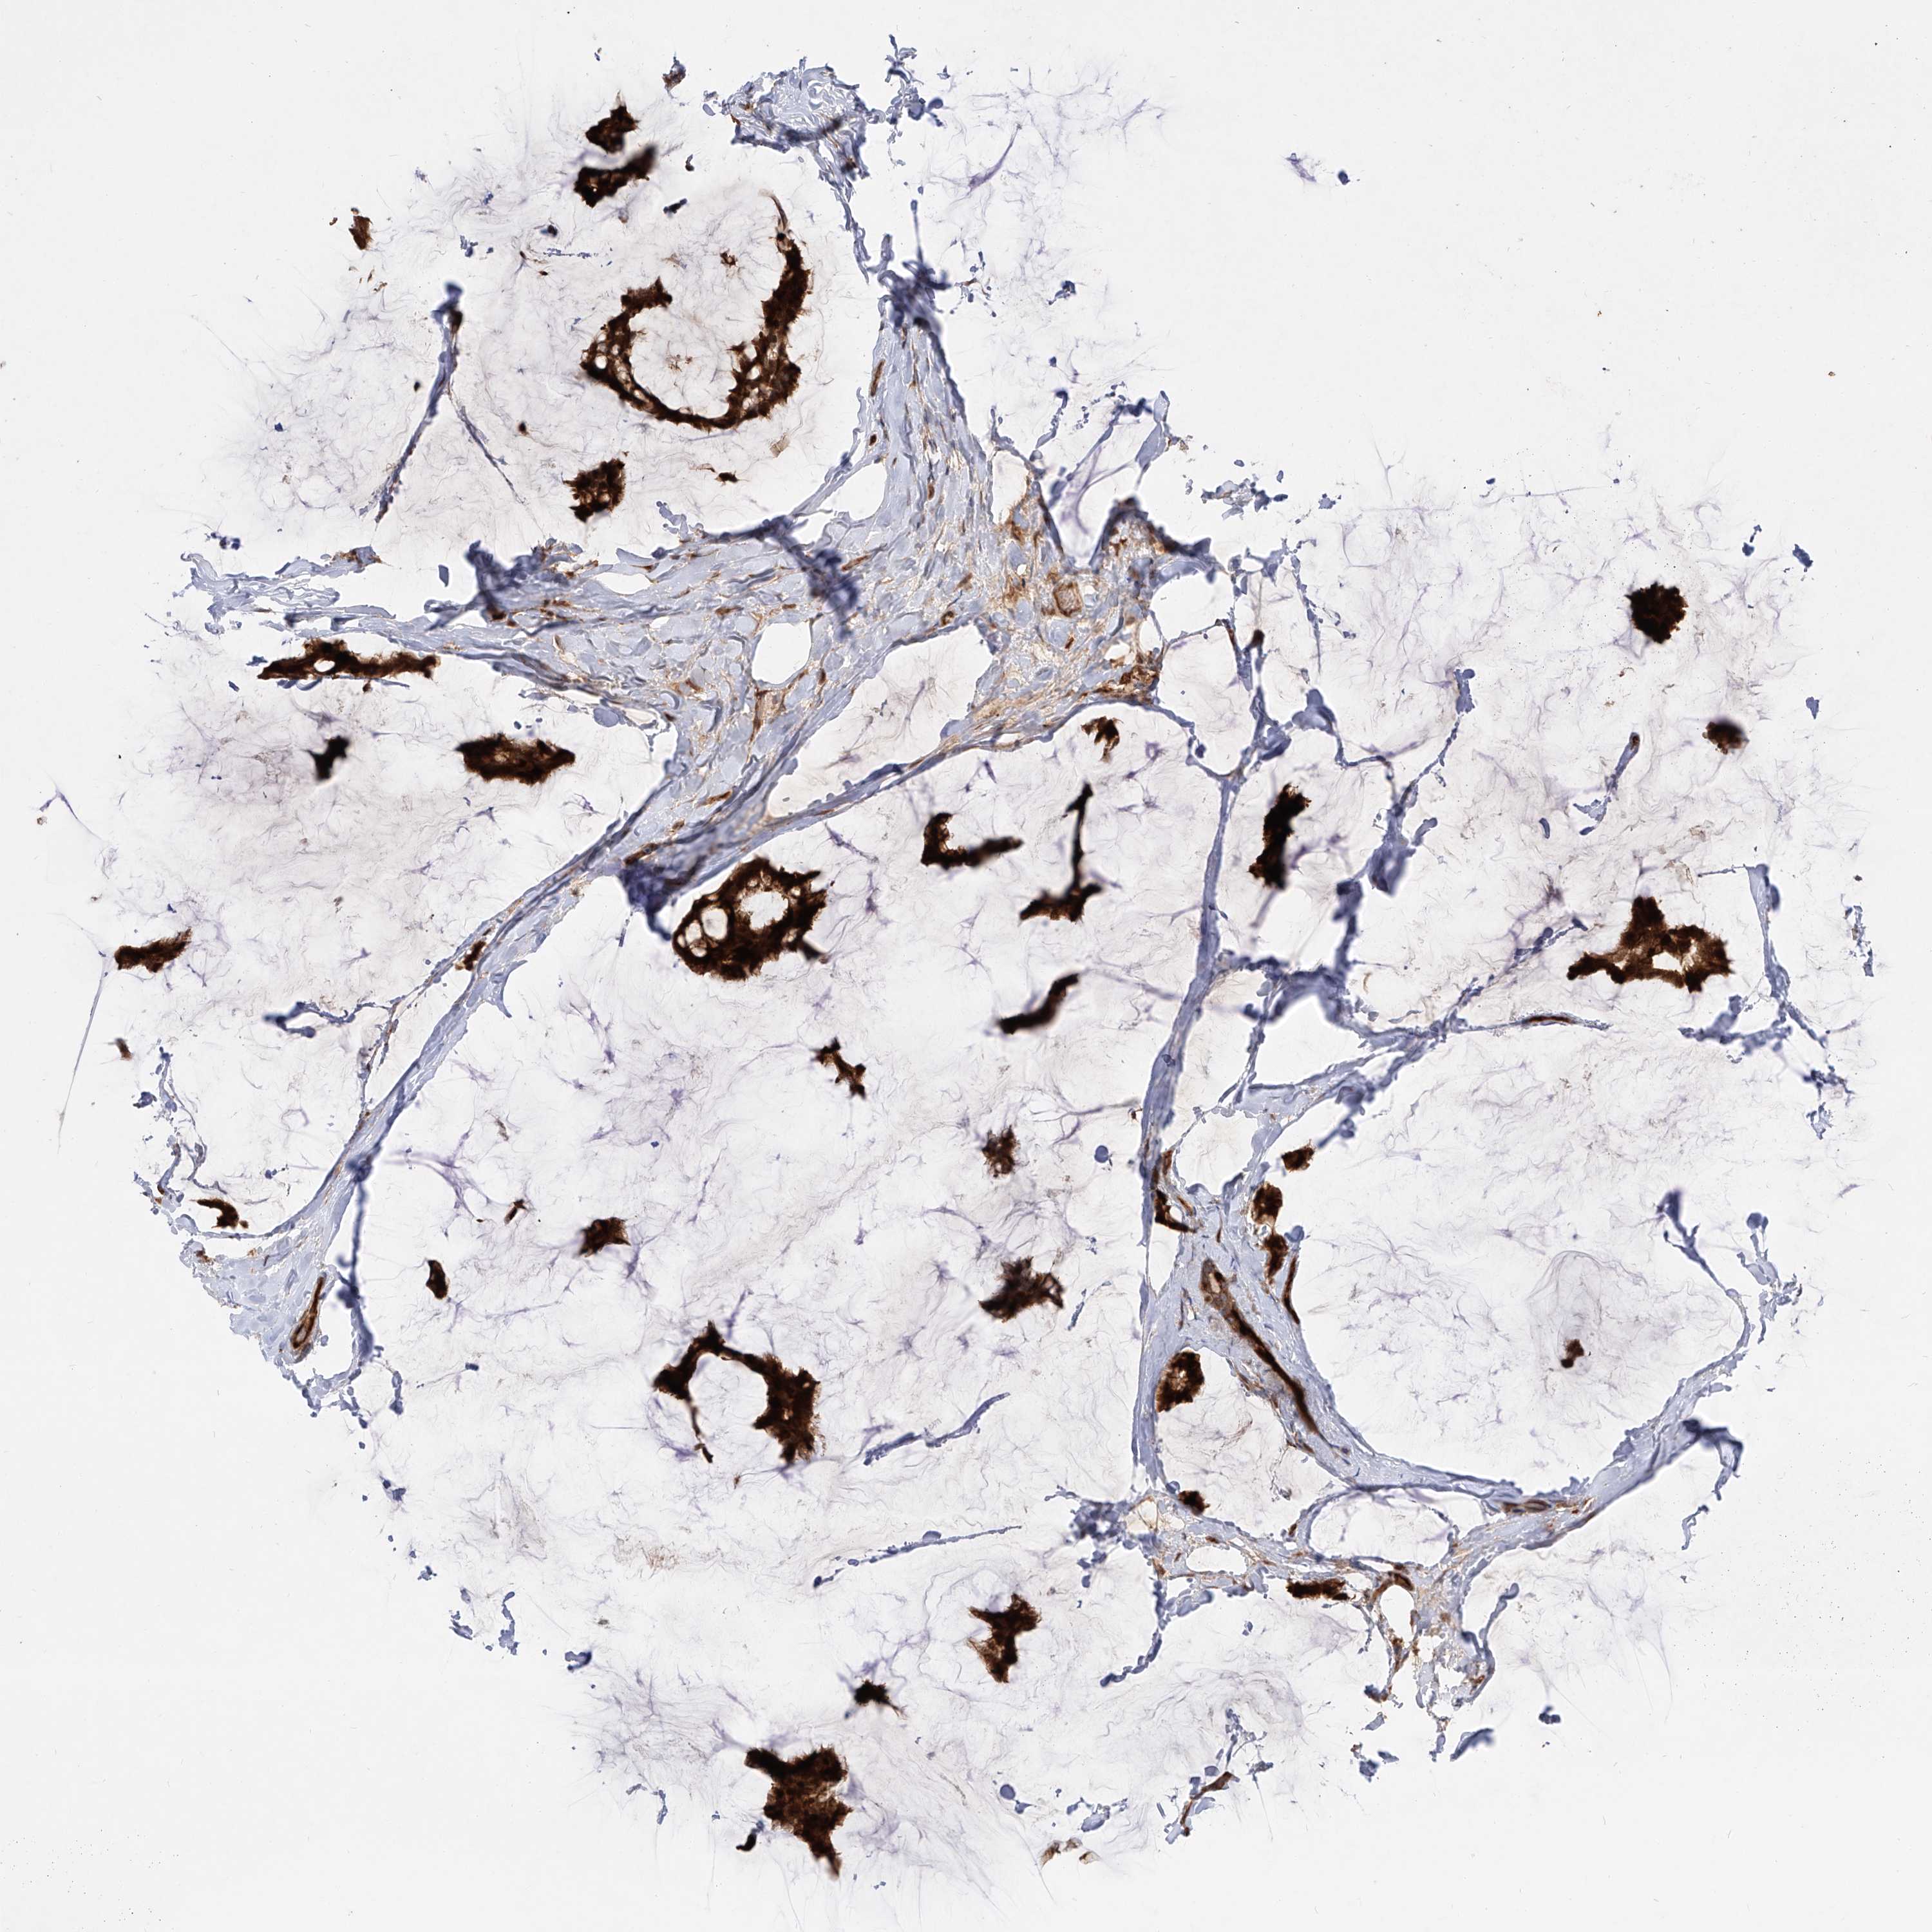

BRCA TCGA BRCA VALIDATION PROTEIN EXPRESSION